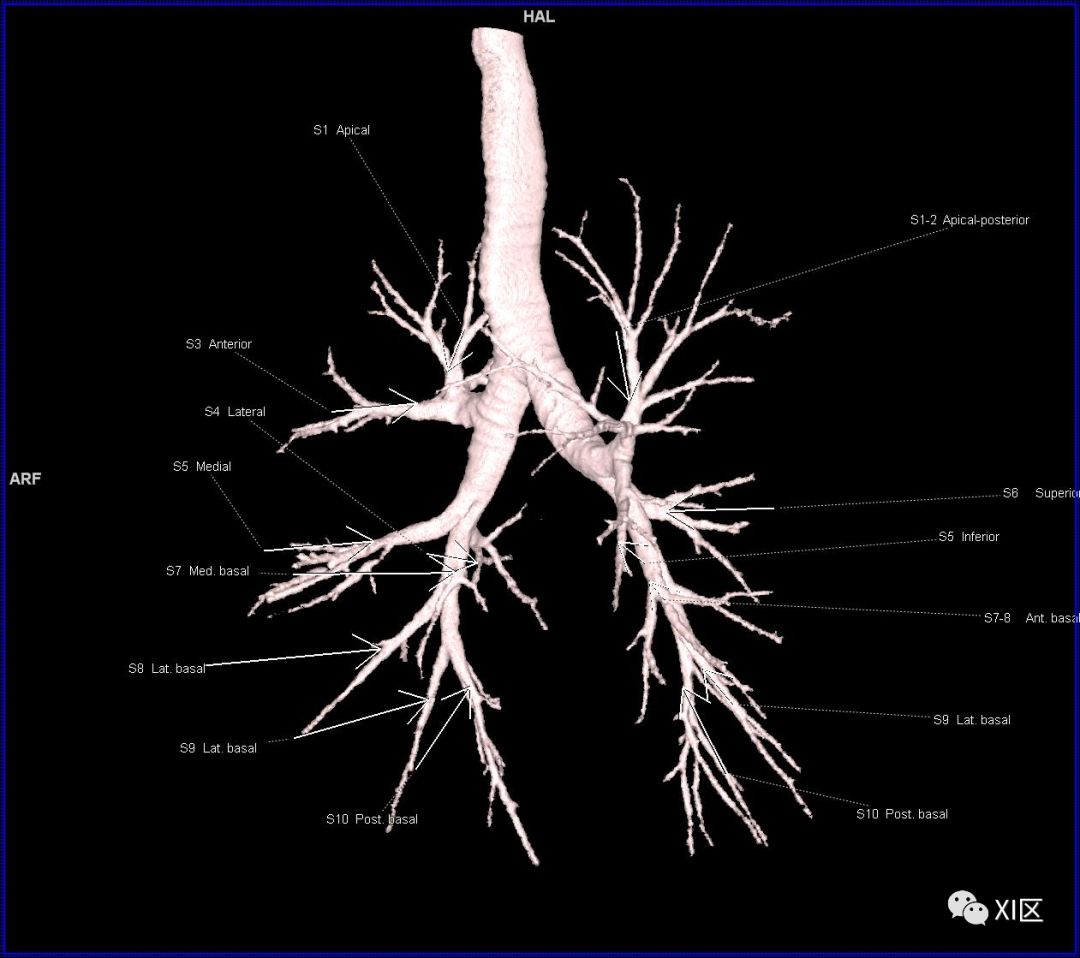

段支气管的命名

段支气管的命名(图片源自网络)

人的支气管(第1级)至肺泡约有24级分支。支气管经肺门入肺,分为叶支气管(第2级),右肺3支,左肺2支。叶支气管分为段支气管(第3~4级),左肺8支、右肺10支。段支气管就是肺的分段的依据。段支气管反复分支为小支气管(第5~10级),继而再分支为细支气管(第11~13级),细支气管又分支为终末细支气管(第14~16级)。从叶支气管至终末细支气管为肺内的导气部。终末细支气管以下的分支为肺的呼吸部,包括呼吸细支气管(第17~19级)、肺泡管(第20~22级)、肺泡囊(第23级)和肺泡(第24级)。

在进行肺的分段时,可以上下观察浏览,沿着相应气管的走形可以更容易准确地进行分段。